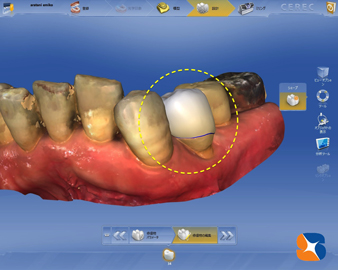

左図は、患者様に合った歯の大きな、長さ、厚みをDr.がPC内で設計したところです。

このデーターを、セラミックブロックを削る器械に送信すれば、短時間で白い歯が出来上がります。

左図は、患者様に合った歯の大きな、長さ、厚みをDr.がPC内で設計したところです。

このデーターを、セラミックブロックを削る器械に送信すれば、短時間で白い歯が出来上がります。